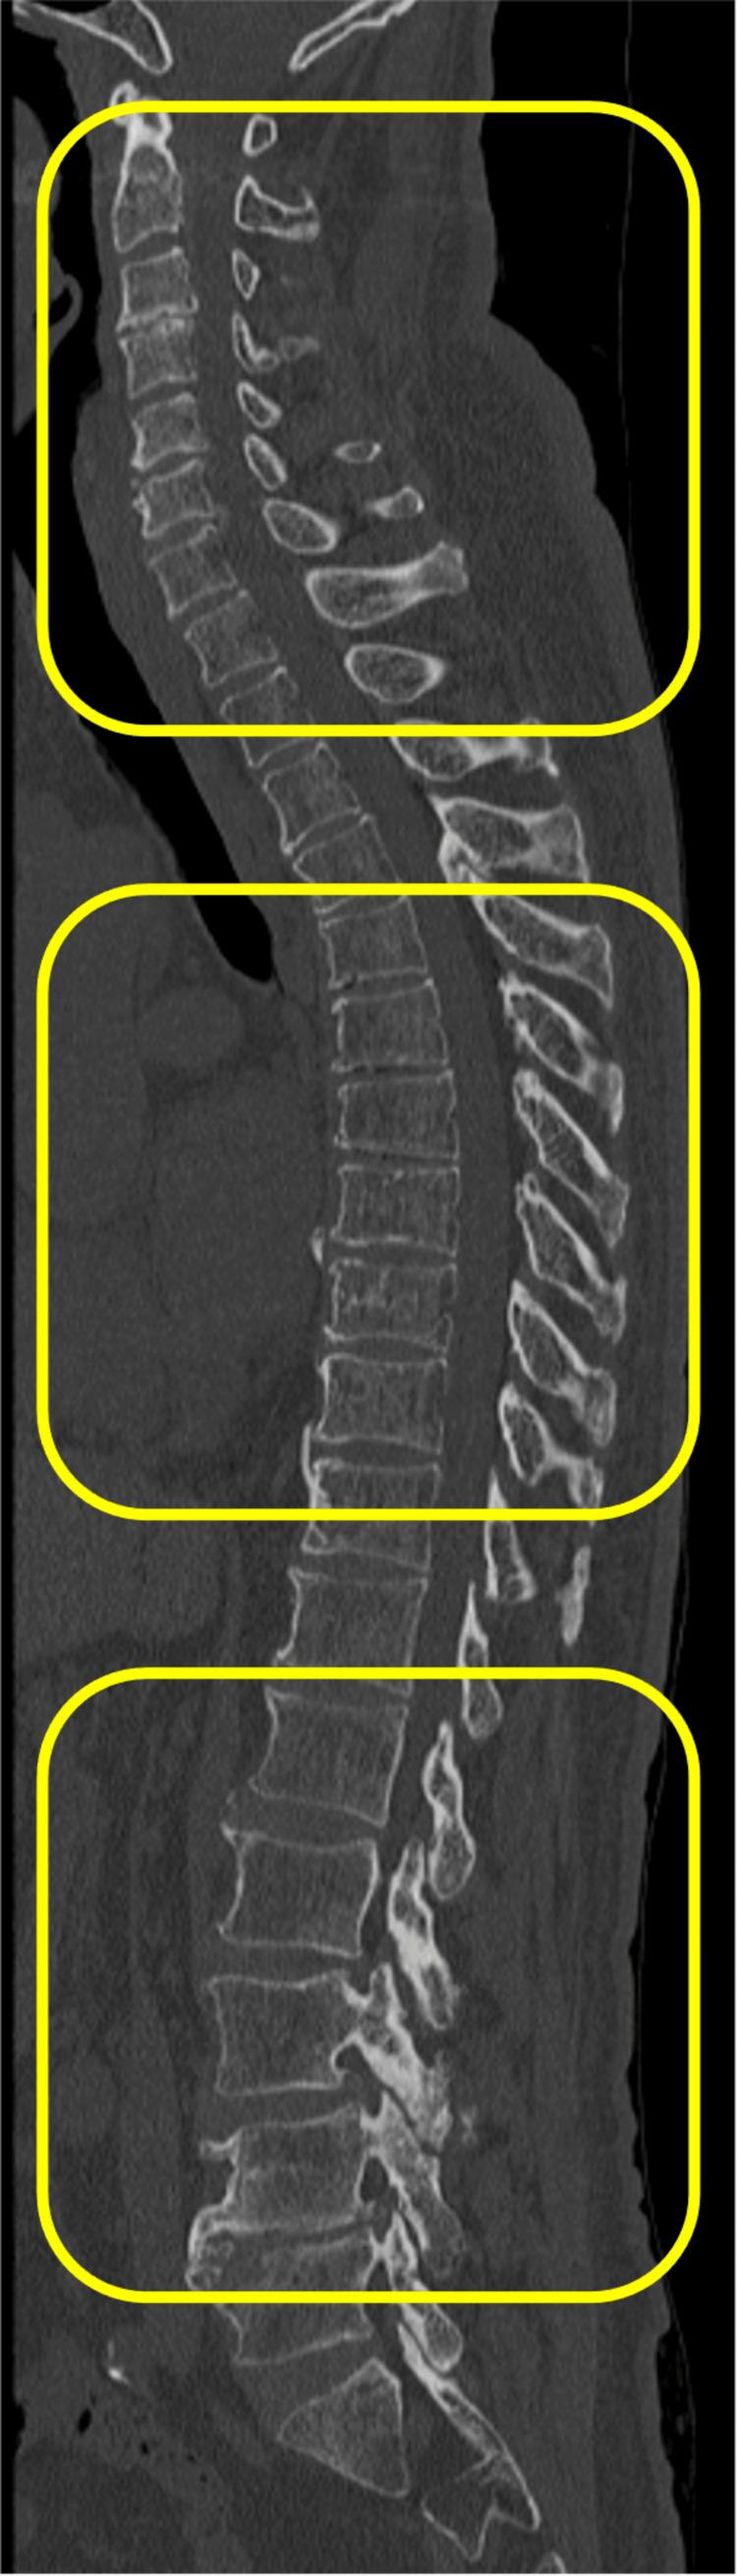

这项回顾性队列研究纳入了2022年1月至2023年3月期间在我院接受脊柱手术治疗的99例年龄≥60岁的连续患者。在全脊柱CT矢状面图像上测量颈椎、胸椎和腰椎椎体背侧的皮肤厚度。根据中位数,将皮肤厚度以4mm的中位数为界分为两组。评估骨密度(BMD)。将前纵韧带和后纵韧带的椎体及椎间桥接骨赘总和定义为OALL指数和OPLL指数。测量血清骨代谢相关标志物水平,如抗酒石酸酸性磷酸酶5b、前胶原I N端前肽、25-羟基维生素D和骨膜蛋白。为评估皮肤厚度与影像学表现之间的关联,我们计算了调整后的比值比,对年龄、性别和体重指数(BMI)进行了校正,并使用单因素和多因素逻辑回归分析。

结果

颈椎、胸椎和腰椎三个背侧区域的皮肤厚度(中位数分别为3.3mm、3.5mm和3.4mm,p = 0.357)以及骨代谢相关标志物之间未发现显著差异。校正年龄、性别和BMI后,颈椎、胸椎和腰椎皮肤厚度分别与DISH、OPLL指数以及OPLL和OPLL指数相关。